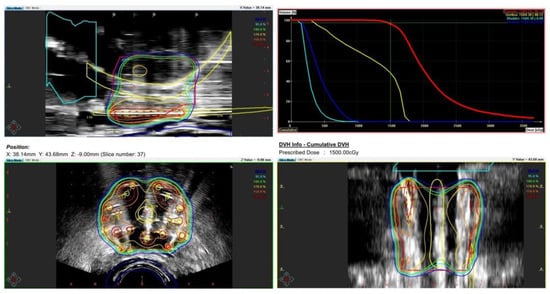

During the planning phase of the radiotherapy treatment course, a PET/CT scan was performed to delineate the metastatic sites accurately and guide radiotherapy planning. The radiotherapy regimen included teleradiotherapy targeting the prostate and affected lymph nodes with radical intent, utilizing a simultaneous integrated boost (SIB) approach with 45 Gy/60 Gy delivered in 25 fractions (Figure 2). Additionally, a high-dose–rate (HDR) brachytherapy boost of 15 Gy was administered in a single fraction to the prostate to achieve maximum local control (Figure 3).

Figure 3. Radiotherapy treatment planning—boost BRT 15 Gy/1 fx. The treatment plan outlines the prostate-focused brachytherapy boost aiming for optimized tumor control while minimizing toxicity. The accompanying dose–volume histogram illustrates the dose distribution within the prostate, urethra, bladder, and rectum.